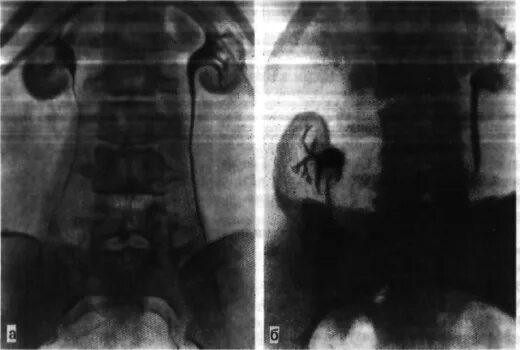

Нефроптоз почки слева